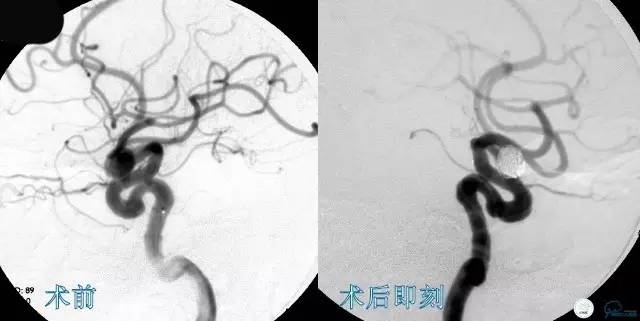

Case3 左ICA床突旁动脉瘤术后复发

术前VS术后即刻